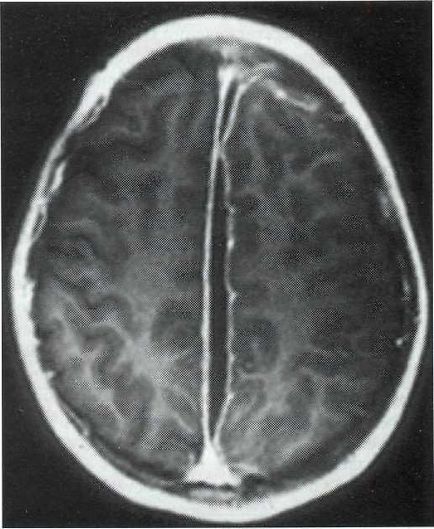

Meg kell jegyezni, hogy amellett, hogy a tipikus convexital formák találhatók esetenként szubdurális gennygyülem, és egyéb területek (ábra. 22-4).

Ábra. 22-4. MRI, axiális szeletet. Subduralis empyema félgömb alakú lokalizáció.